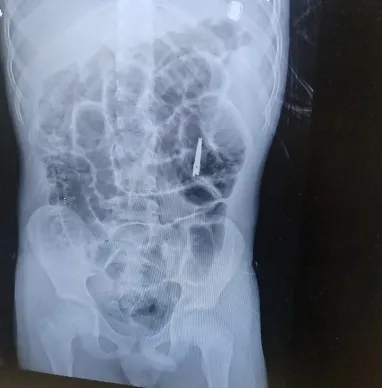

כשי' נמצא בהרדמה מלאה בחדר הניתוח, בוצע צילום נוסף כדי לבחון את מיקום ומצב המספרים. בצילום התברר כי המספריים נסגרו מעצמם, עברו את הקיבה והגיעו לעומק המעי הדק. "הייתה סכנה שהמספריים הפתוחים יגרמו לפציעה לושט או לקיבה ורצינו לבצע בדיקה על מנת לאתר ולשלוף אותם", אומרת ד"ר אסתר אורלינסקי-מאייר, מומחית בגסטרואנטרולוגיה ילדים בשערי צדק. "באורח פלא ומסיבה לא ברורה, ראינו שהמספריים נסגרו מעצמם, כך שהסכנה לפציעה בדרכי העיכול פחתה".